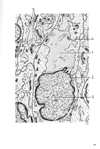

交連下器官【こうれんかきかん】 Area of ependyma cells lying anterior to the tectum of midbrain at the beginning of the cerebral aqueduct.(交連下器官は、後交連の下で、第三脳室と中脳水道との接合部にある上衣細胞からなる器官。この器官の機能は不明である。)